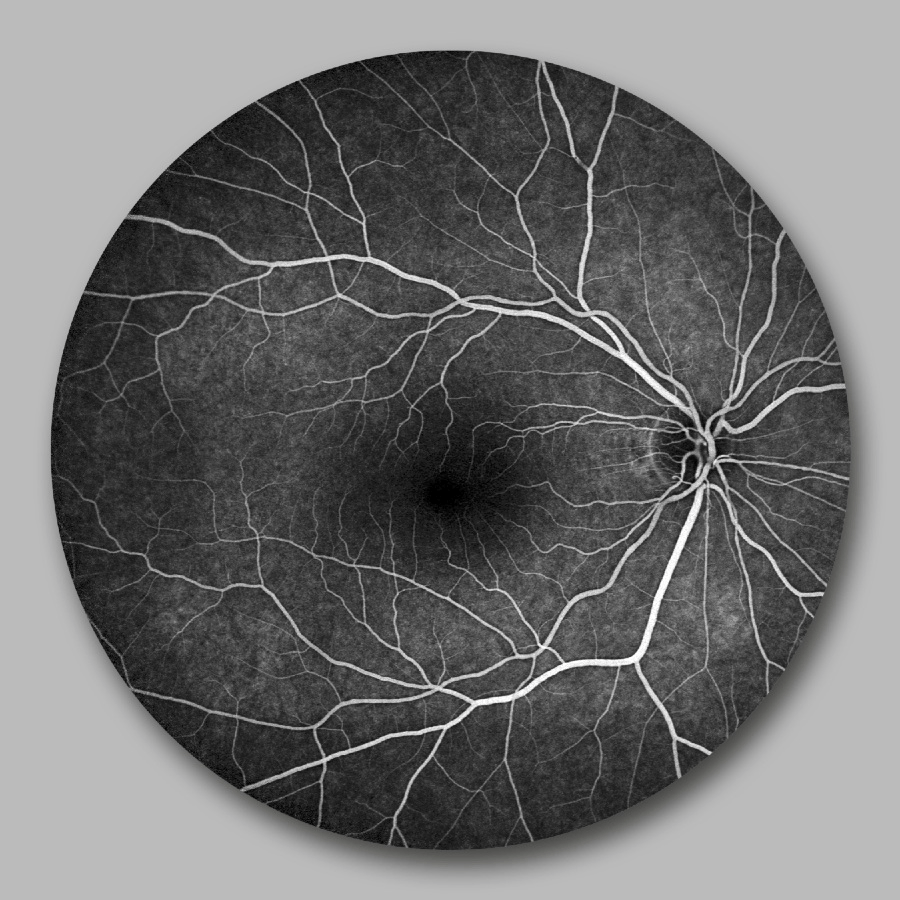

Hier sehen Sie eine Auswahl unserer innovativen Diagnosegeräte, die präzise Analysen ermöglichen und eine frühzeitige Erkennung von Augenerkrankungen unterstützen. Klicken Sie auf „Weiteres“, um Informationen zu den einzelnen Geräten zu erhalten.